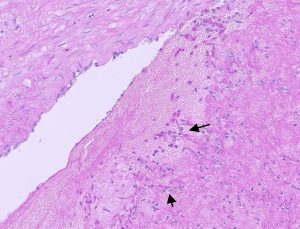

Figure 3 : Lung histopathology from a sheep showing lymphohistiocytic interstitial pneumonia with macrophages in alveoli (circles) and smooth muscle hyperplasia (arrows) suggestive of maedi visna (MV).